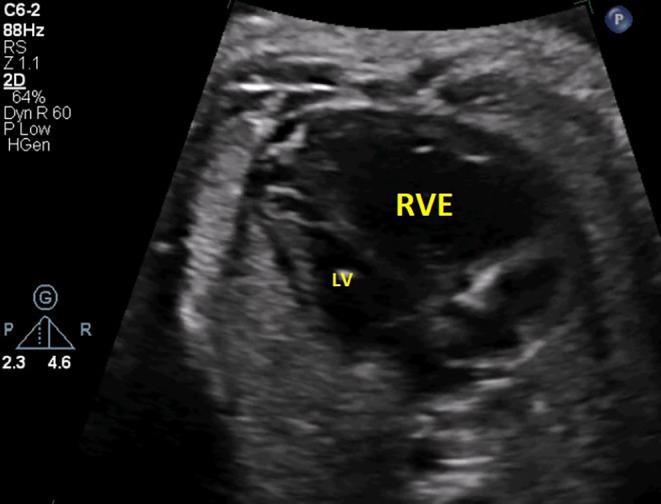

Premature Constriction of Fetal Ductus Arteriosus Caused by Sertraline in a Pregnant Woman: A Case Report.

Fetal ductus arteriosus was treated in a 39-year-old pregnant woman in the 33rd week After psychiatric consultation and discontinuation of sertraline which underscores the association of sertraline with premature ductus arteriosus constriction.

一名39岁的孕妇在孕33周时接受了胎儿动脉导管相关治疗。经过精神科会诊并停用舍曲林治疗,这突出了舍曲林与动脉导管过早收缩之间的关联。